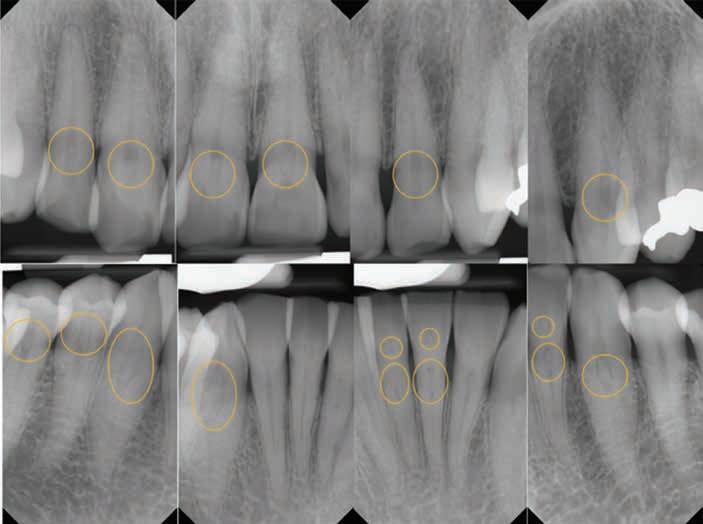

Dental Evidence Recovered: Maxilla and Mandible

Maxilla Occlusal View

Mandible Occlusal View

Right Left

Right Lateral View

Left Lateral View

Right Left Left Right

Dental Postmortem Radiographs

DCME Case #25-06904: